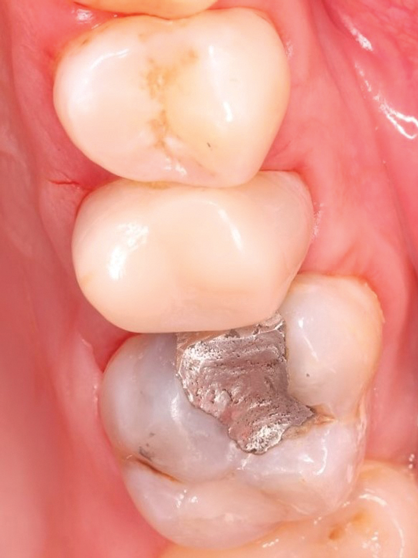

IOSs have found extensive applications across various dental specialties.1 In restorative dentistry, they are primarily used for fabricating dental restorations through CAD/CAM workflows, which remains by far their most widespread use (Figure 1 through Figure 5).2 The accuracy of IOSs enables dental professionals to produce restorations with precision that is on par with conventional methods.3 In addition to restorative dentistry, IOSs are being utilized for various applications in prosthodontics, orthodontics, forensic dentistry, and oral and maxillofacial surgery.

Fig 1 through Fig 5. Single-visit restoration of a maxillary second premolar following root canal treatment. Fig 1: Morphology-guided overlay preparation. Fig 2: IOS bite registration via imaging of buccal tooth surfaces. Fig 3: Preparation margin defined following IOS impression. Fig 4: Overlay design on the IOS platform, integrating adjacent tooth anatomy. Fig 5: Bonded overlay fabricated from CAD/CAM resin-based composite. Fig 6 through Fig 9. Digital workflow for guided endodontics using a digital twin, created by registering an IOI with CBCT data.

Figure 3